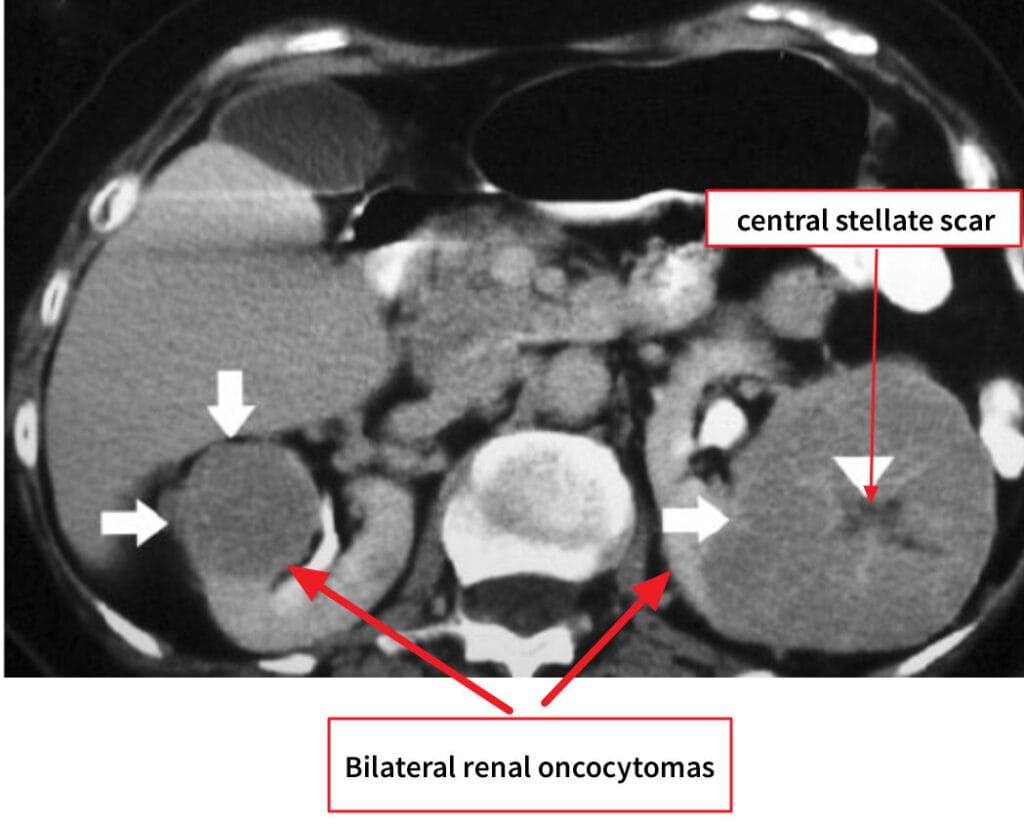

Renal Oncocytoma

[정의]

미토콘드리아가 풍부한 집합관 유래의 양성 상피성 종양입니다.

영상학적으로 RCC(특히 chromophobe)와 감별이 어려울 수 있습니다.

[원인/위험요인]

– 명확한 환경 위험요인은 제한적이며, 드물게 Birt–Hogg–Dubé 증후군과 연관됩니다.

[임상양상]

– 대부분 무증상 우연 발견

– 드물게 혈뇨·옆구리 불편감을 유발합니다.

[진단]

– CT/MRI에서 중심성 반흔이 보일 수 있으나 특이적이지 않습니다.

– 생검으로 진단을 시도하되, 불확실 시 신보존 수술을 고려합니다.

[치료]

– 작은, 확실한 양성 의심 병변은 능동 감시가 가능합니다.

– 감별 불가·성장·증상 시 부분 신절제를 우선합니다.

– 다발성 또는 기능 보존 필요 시 국소 열치료(냉동/고주파)를 선택적으로 고려합니다.